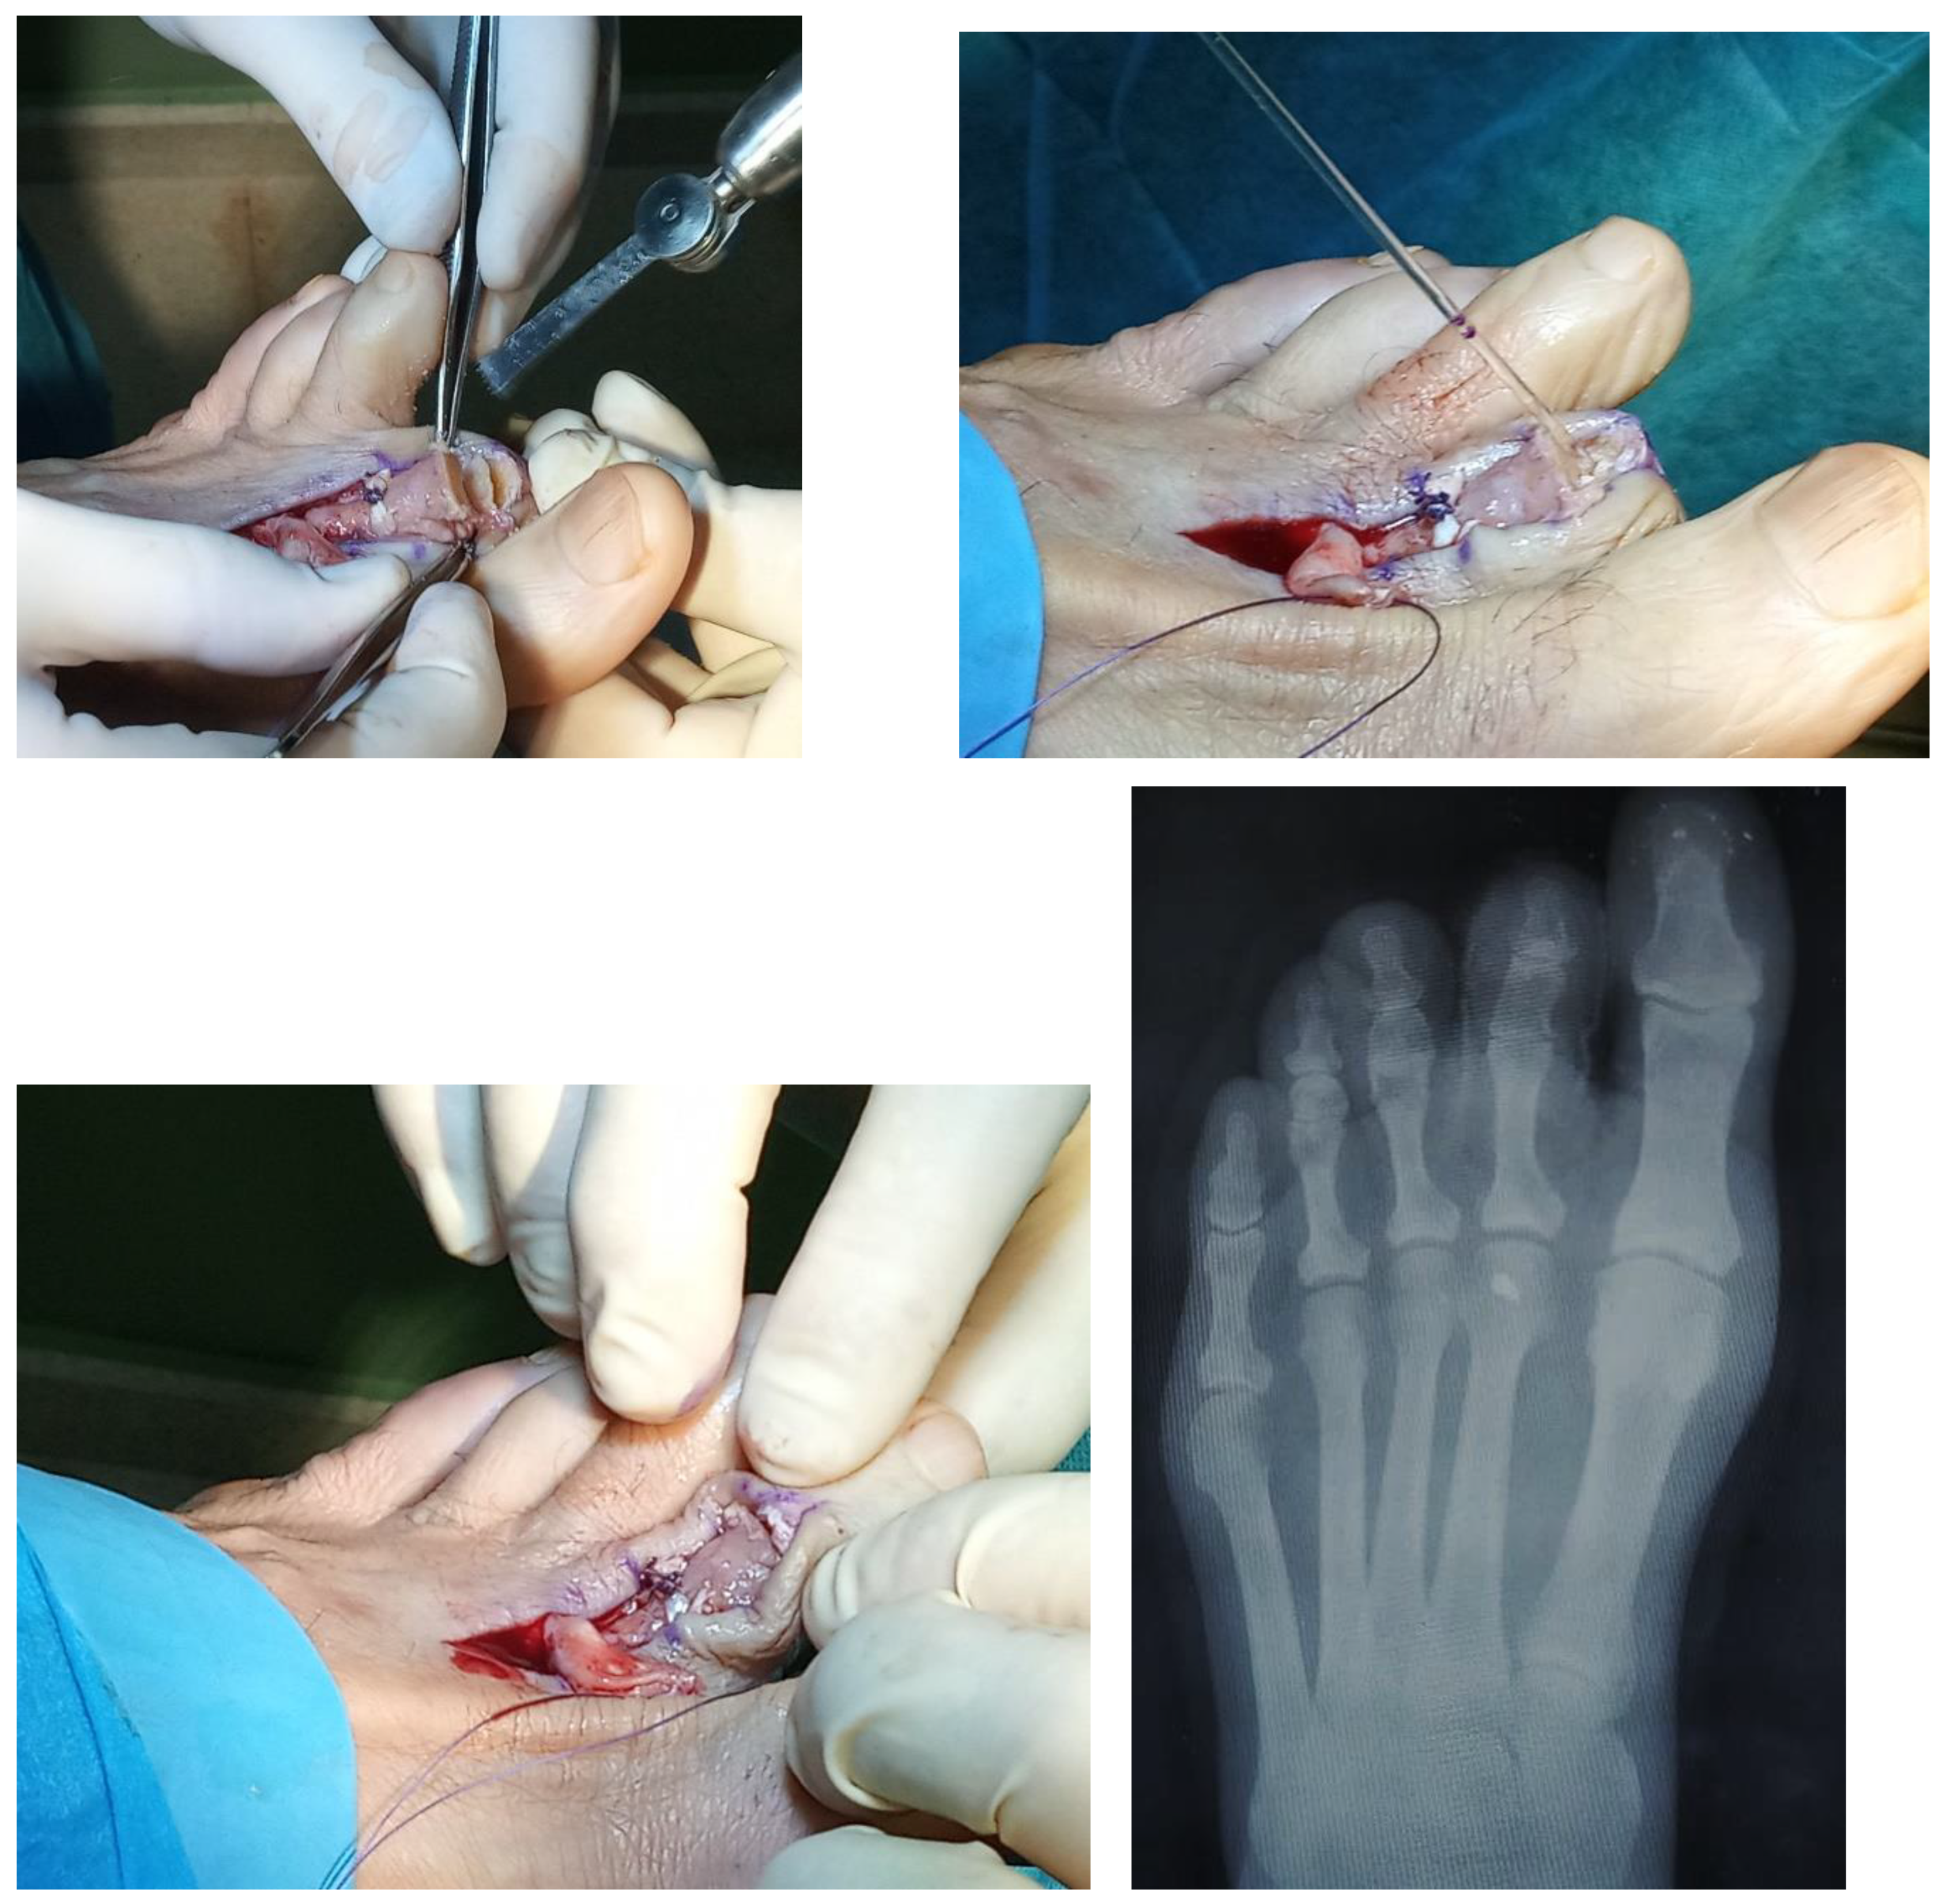

A 64-year-old male presented with progressive metatarsalgia refractory to plantar orthosis after three years of treatment in the left foot. Physical examination of the second MTPJ showed little swelling, no second toe purchase, very positive drawer test, and fixed clawtoe without plantar hyperkeratosis. The weight-bearing anteroposterior radiographic examination shows a subluxed second MTPJ, dorsiflexion of the proximal phalanx, and degenerative proximal interphalangeal joint (Figure 1). In the longitudinal ultrasound image, the extensive tear visible through dynamic dorsiflexion manoeuvres of the affected toe could be visualized as a focal hypoechoic distal defect. The surgical procedure proposed was flexor- to- extensor tendon transference associated with metatarsal osteotomy and interphalangeal arthrodesis. Using the dorsal approach, a curved S-shaped incision was made that extended the MTPJ to the proximal interphalangeal joint (PIPJ). The PIPJ was identified and the extensor tendon was transected and reflected proximally all the way to the MTPJ capsule. The collateral ligaments were then released, and the articular surfaces were minimally removed. Subsequently, the extensor tendon was removed from the Hood apparatus and the MTPJ capsule was incised and released using a McGlamry elevator to reduce contracture. Using a sagittal saw, a second metatarsal Weil osteotomy was performed to decompress MTPJ and to recompose the metatarsal parabola. The osteotomy was fixed in the desired position with one small snap-off self- tapping screw. With ankle plantarflexion to relieve tension and using a curved hemostat, FDL was identified and freed from the attachment of soft tissues and clamped and cut as distal as possible. The FDL was split longitudinally, and the tails passed in the medial and lateral aspects of the base of the proximal phalanx. With the toe placed in 20 degrees of plantar flexion of the MTPJ, the tails of the FDL were dorsally crossed and sutured with the appropriate tension and the desired rest position slightly distal to the base of the proximal phalanx. Subsequently, end-to-end proximal arthrodesis of the proximal interphalangeal joint was performed using an absorbable pin of polylactic acid. The extensor tendon was conveniently sutured and routine wound closure was performed. The postoperative compression dressing was applied and the patient was discharged home on the postoperative day. After a five-month follow-up period, the patient returned to normal function and has markedly improved the stability of the affected MTPJ in the absence of pain.

Figure 2. Surgical image sequence of the procedure performed and postoperative radiographic aspect corresponding to case 1.